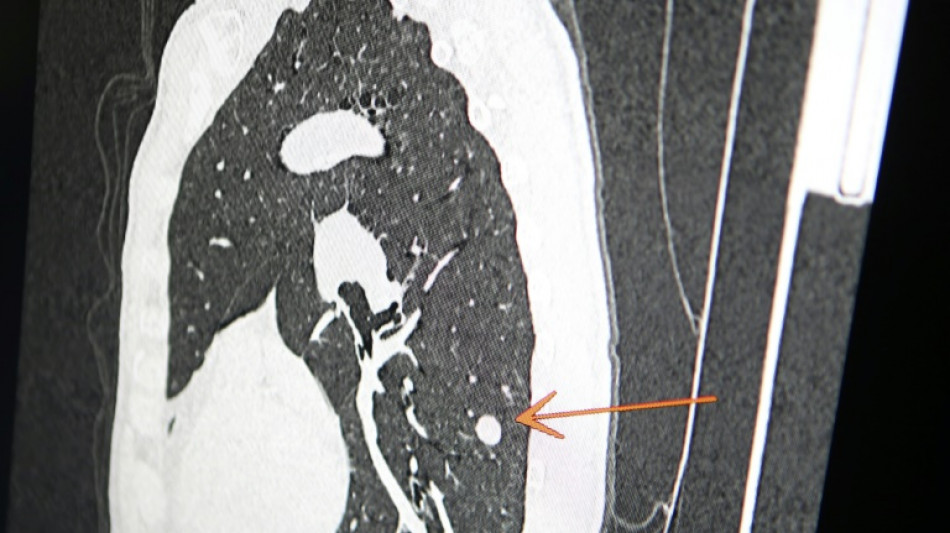

"Usted tiene cáncer", mensaje erróneo y aterrador a cientos de pacientes de una clínica en Inglaterra / Foto: Pascal Pochard-Casabianca - AFP/Archivos